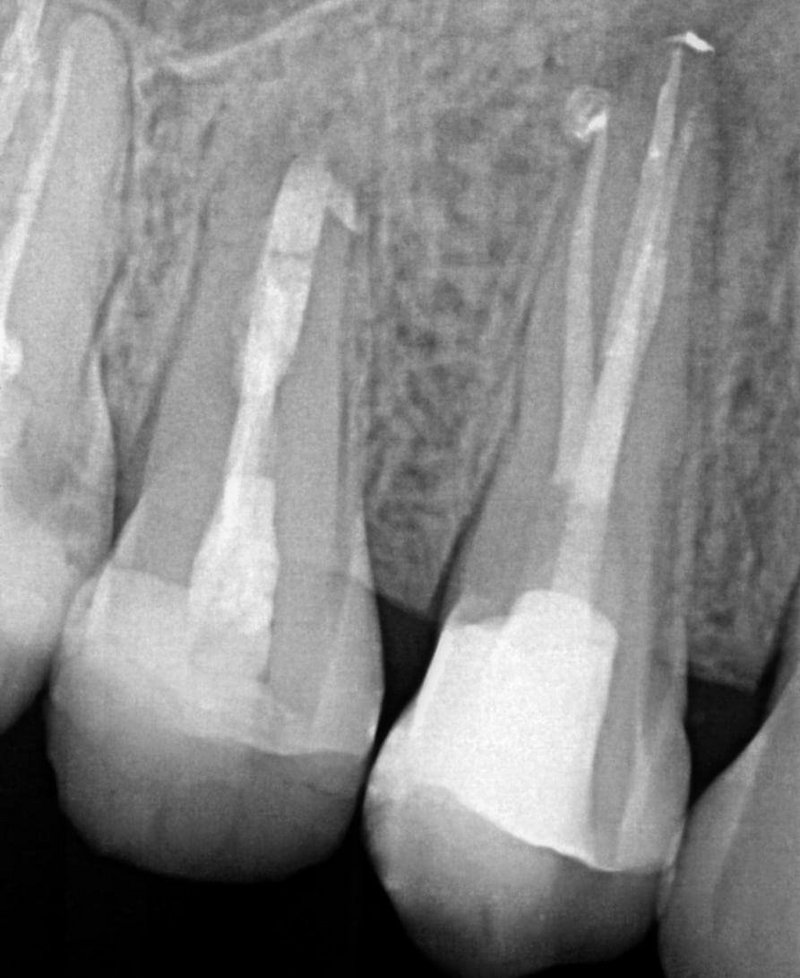

Dr. Johannes Stemmann

Bei einer klinischen Nachkontrolle zwei Wochen postoperativ im Rahmen der Weiterversorgung gab die Patientin an, keinerlei Beschwerden oder Schmerzen nach der Wurzelkanalfüllung gehabt zu haben. Die technisch einwandfrei verlaufende Behandlung darf auf eine baldige knöcherne Ausheilung hoffen lassen. Eine erste radiologische Nachkontrolle ist in sechs Monaten geplant. Für eine langfristig gute Prognose wird der Zahn zeitnah mit Zahnersatz aus dem hauseigenen Labor versorgt. Die Patientin bedauerte im Nachgespräch, für die Wurzelbehandlung nicht von Anfang an eine Praxis mit entsprechender technischer Ausstattung und spezialisierten Zahnärzte aufgesucht zu haben. Sie zeigte sich sehr erleichtert, dass der Zahn nicht extrahiert werden musste. Im Anschluss an die beschriebene Behandlung wurden zwei weitere Revisionen an Zahn 15 und 16 im AllDent Zahnzentrum Bremen durchgeführt.